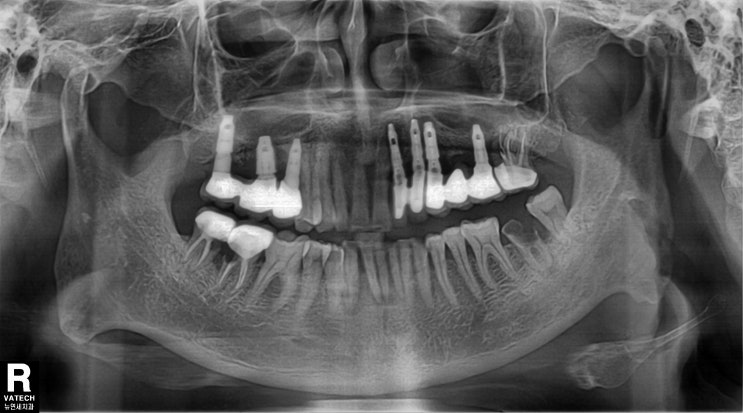

뿌리까지 충치 먹은 자연치아를 포스트 크라운으로 살려쓰기

여기저기 문제가 많지만 특히 오래전 씌운 하악우측 구치 2개를 뽑고 임플란트를 하라는 진단을 받은 분입...